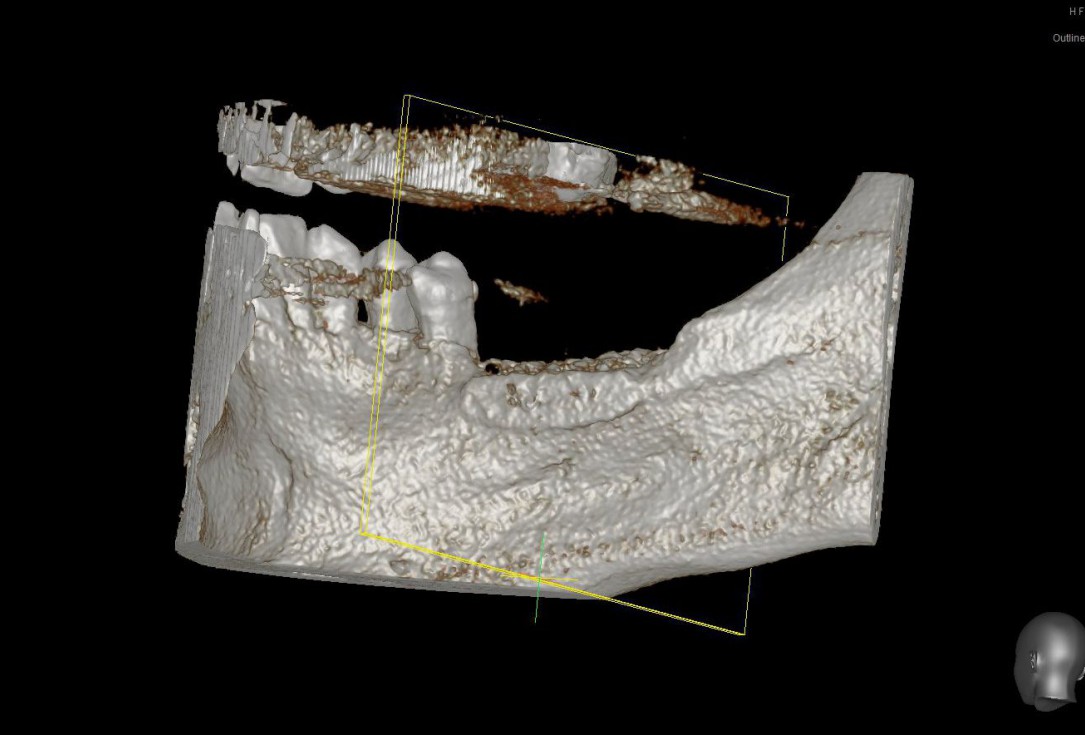

02/28 - Model of the initial defect computed from a CBCT scan - lingual viewThree-dimensional augmentation with maxgraft® cortico - Dr. R. Würdinger